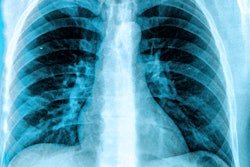

The software, qXR-LN, will serve as a “second read” alongside radiologists to improve detection of subtle lung nodules and generate evidence for future AI research, Qure.ai said. The partnership will bring AI-powered early detection to routine chest x-rays, flagging potentially cancerous lung nodules earlier and helping identify high-risk patients, the company said.